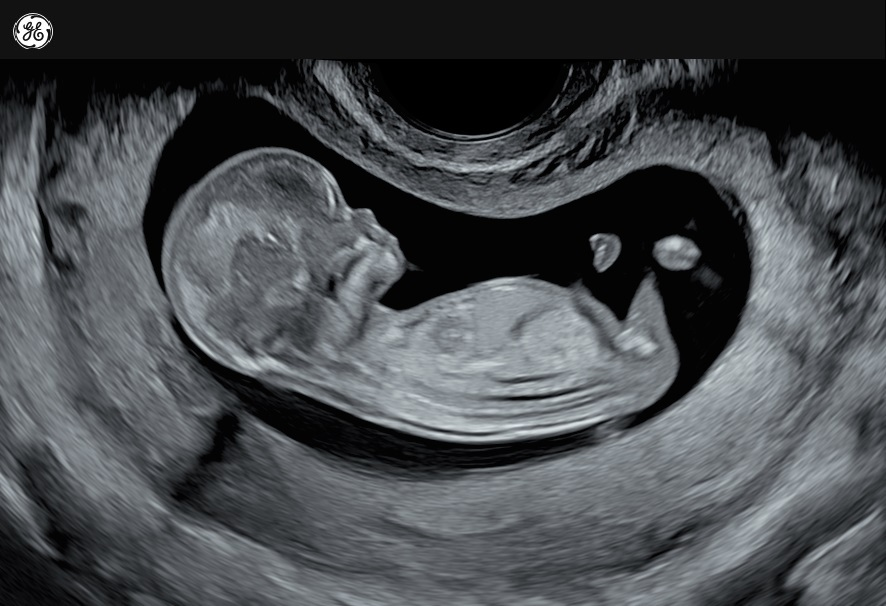

Why is the story of Abby Johnson so powerful? Why has it lit a fire in the souls of so many? Perhaps it is because Abby has seen both sides of the story. Often, the most convincing witnesses are those who believed the lie and later found the truth. Abby was completely and totally immersed in the abortion industry, even receiving an award from Planned Parenthood in 2008. She even had two abortions herself, now mourning the children she never got to meet. But she never realized just how violent and cruel the procedure was until she was told to hold the ultrasound probe during a demonstration.